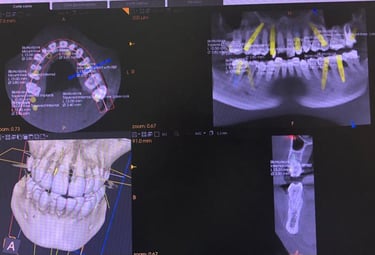

Trabajamos bajo un principio irrenunciable: mínima invasión, máxima precisión. Cada intervención se planifica de forma personalizada, buscando el equilibrio entre salud, función y estética. Combinamos protocolos basados en evidencia con diagnóstico digital, flujos CAD/CAM, guías quirúrgicas y materiales de última generación para obtener resultados naturales y duraderos, evitando procedimientos innecesarios.

NUESTROS CASOS REALES